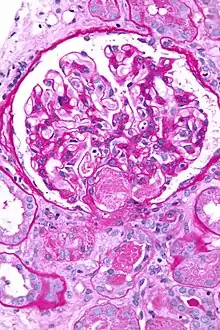

Micrograph showing acute thrombotic microangiopathy due to DIC in a kidney biopsy. A clot is present in the hilum of the glomerulus (center of image).